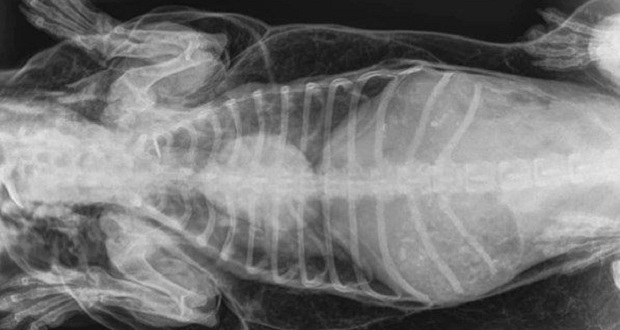

Al llegar al veterinario, profesionales le hicieron radiografías y encontraron que el animal tenía un orificio en su tráquea. Cada vez que el salchicha inhalaba aire, se filtraba por ese agujero y el aire ingresaba a sus músculos.